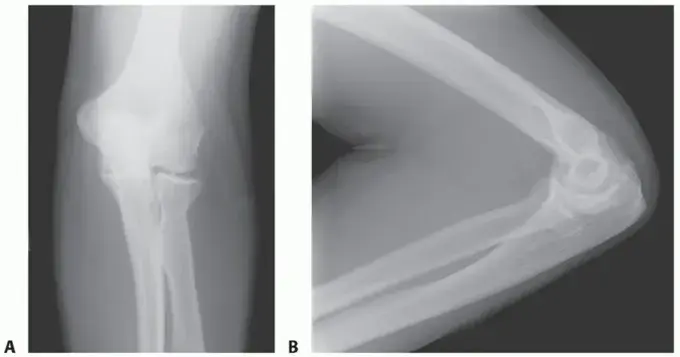

تشريح المرفق المبسط كيف يعمل مفصل ذراعك

لفهم تصلب المرفق، من المهم أن نفهم أولاً كيف يعمل المرفق الطبيعي. المرفق ليس مجرد مفصل بسيط، بل هو تحفة هندسية تسمح لنا بالقيام بمجموعة واسعة من الحركات الضرورية لحياتنا اليومية.

يمكننا تخيل المرفق كمفصلة معقدة تربط ثلاث عظام رئيسية في ذراعك:

1. عظم العضد (Humerus): وهو العظم الكبير في الجزء العلوي من ذراعك.

2. عظم الزند (Ulna): أحد عظمي الساعد، وهو العظم الأكبر والأكثر بروزًا عند المرفق.

3. عظم الكعبرة (Radius): العظم الآخر في الساعد، وهو الذي يدور للسماح لك بقلب راحة يدك لأعلى أو لأسفل.

تتجمع هذه العظام الثلاثة لتشكل ثلاثة مفاصل صغيرة داخل كبسولة مفصلية واحدة، تعمل بتناغم مذهل:

• المفصل الزندي العضدي (Ulnohumeral Joint): هذا هو المفصل الرئيسي الذي يعمل كـ "مفصلة" حقيقية، يسمح بثني وفرد الذراع (مثل مفصل الباب).

• المفصل الكعبري الرأسي (Radiocapitellar Joint): يقع هذا المفصل حيث يلتقي عظم الكعبرة برأس العضد. يسمح هذا المفصل بحركات الانزلاق والدوران الضرورية لقلب الساعد.

• المفصل الكعبري الزندي القريب (Proximal Radioulnar Joint): يقع هذا المفصل بين الزند والكعبرة، وهو المسؤول عن حركة الدوران التي تسمح لك بتدوير يدك.